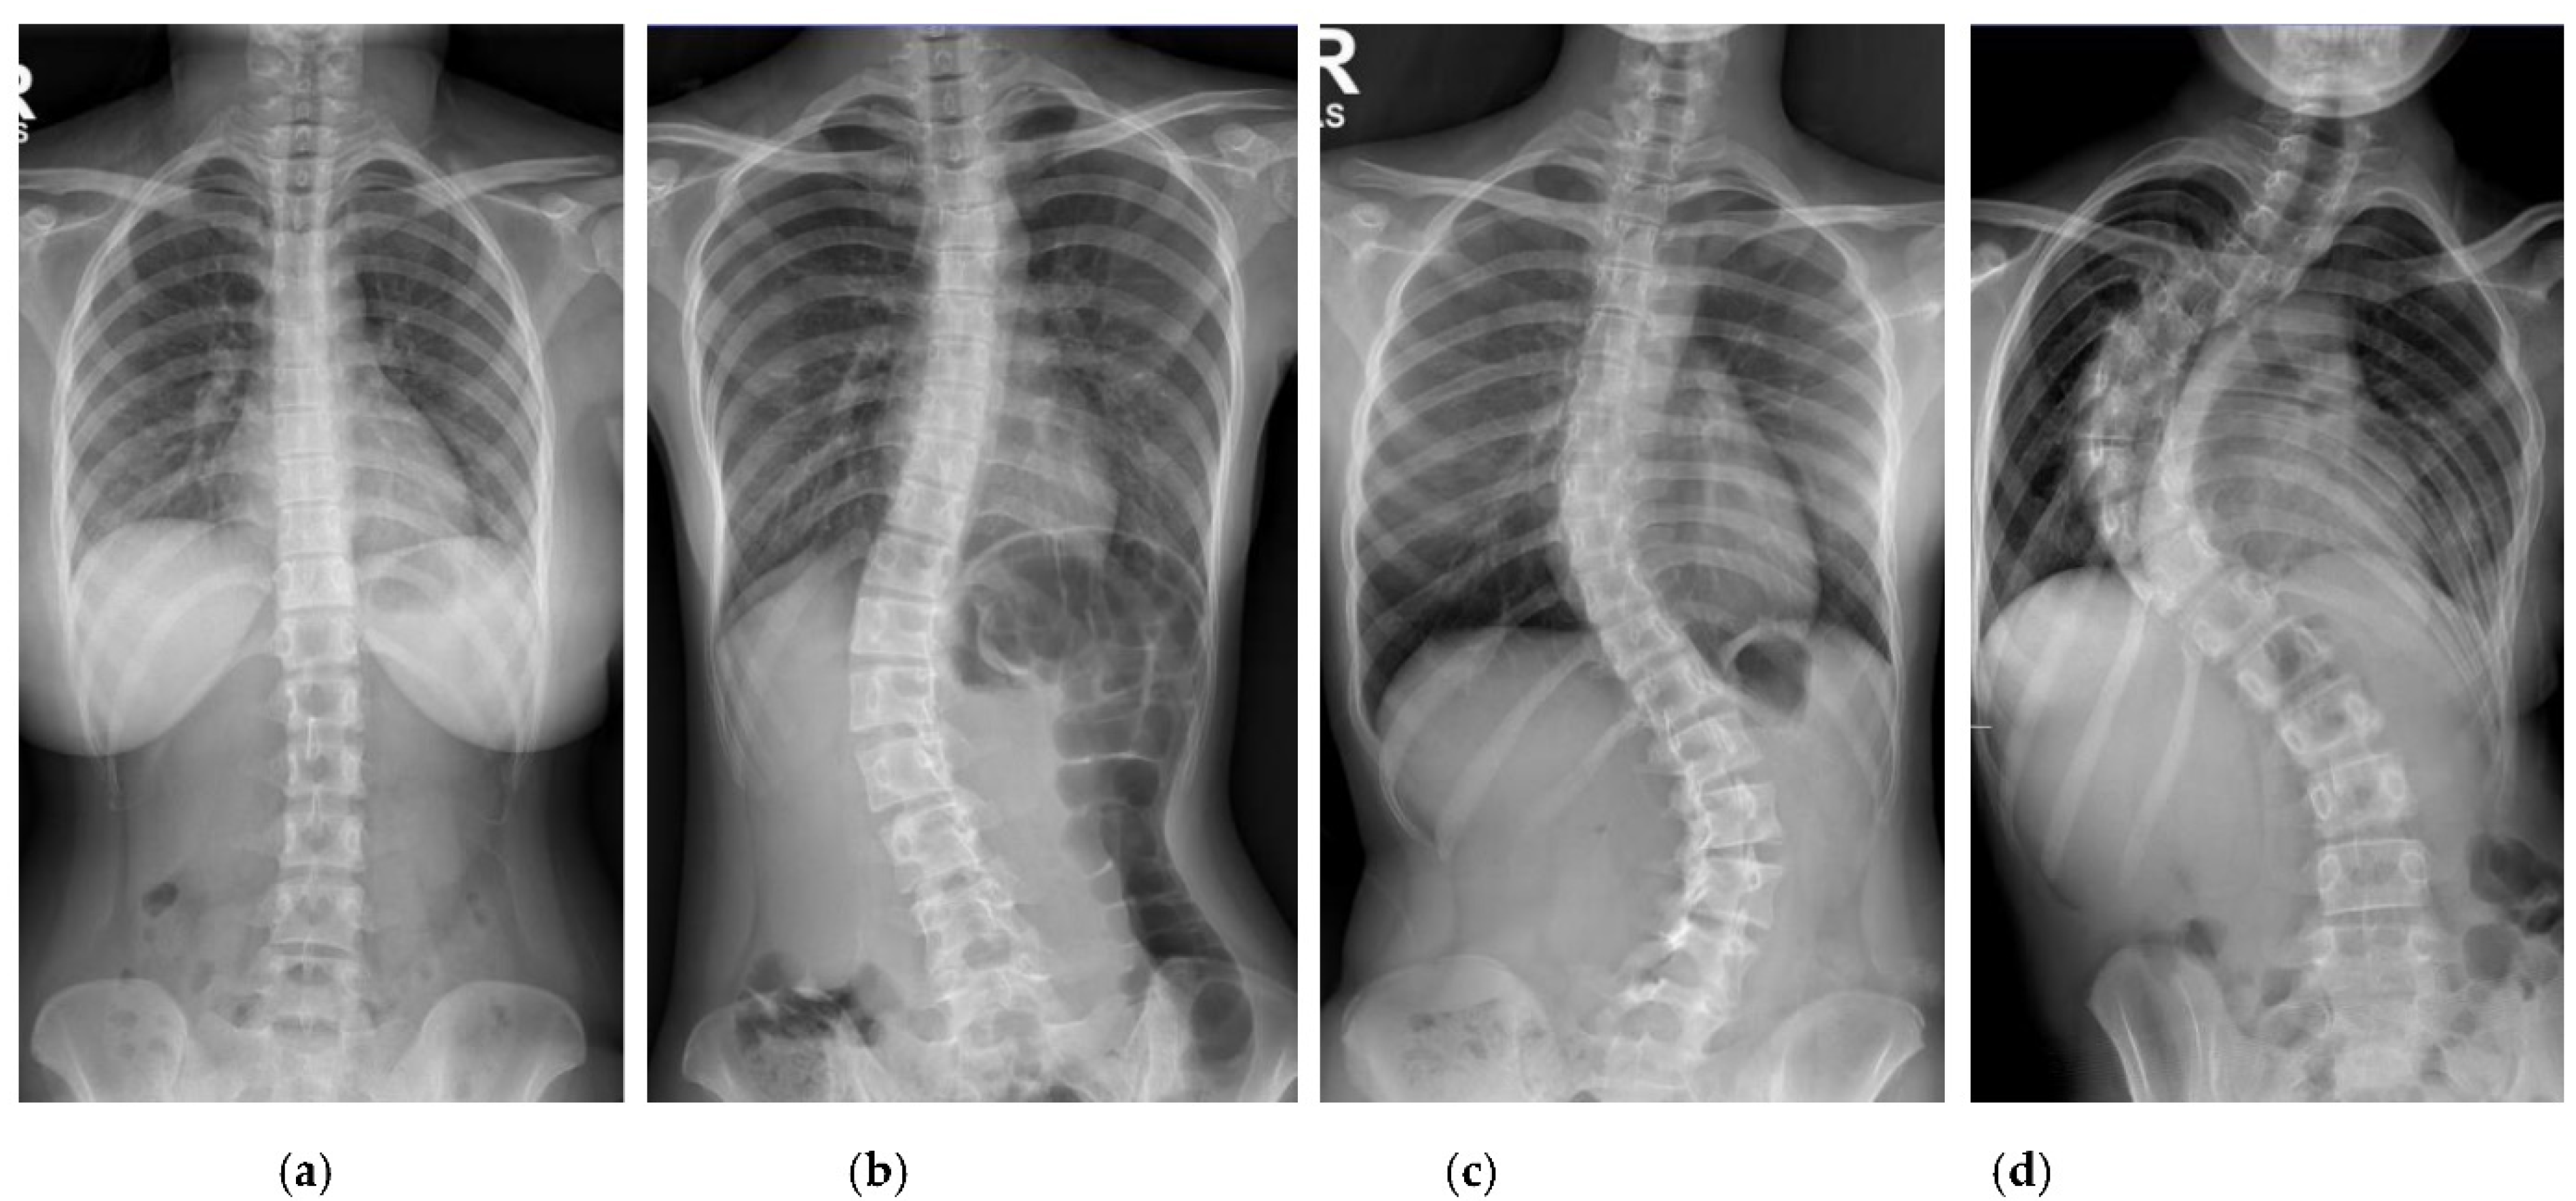

Figure 2.

Examples of standard X-ray images exported from the PACS: (a) CA < 10°; (b) CA 10° to 25°; (c) CA > 25° to 40°; (d) CA > 40°.

Patients with AIS who attended the scoliosis clinic at Pantai Jerudong Specialist Centre from 1 November 2018 to 4 September 2020 were identified from the institution’s scoliosis database. These patients had standard standing anterior-posterior X-rays showing cervical vertebra level 7 to the femoral heads and the entire rib cage from right to left as part of routine clinical management. The X-ray images were retrieved from the institution PACS, anonymized, and exported as a JPEG format image, as shown in Figure 2. The CA for each X-ray image was measured by (1) two neurosurgeons (Observer 1 specializes in scoliosis; Observer 2 does not), who were blinded to each other and the ACAMM, using the in-built function in the PACS and (2) the ACAMM.